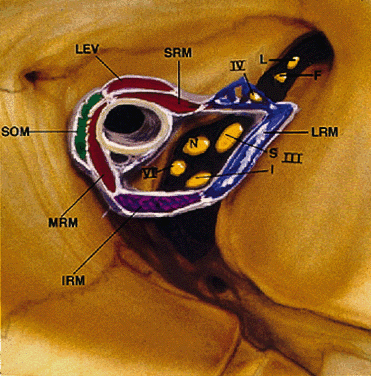

ANNULUS OF ZINN

The annulus of Zinn represents a complex, dense, fibrous band of connective tissue with firm attachments to the periosteum of the orbital apex (Fig. 12). Medially, it is fused to the optic nerve sheath, which may account for the pain during eye movements experienced by patients with optic neuritis. All four rectus muscles arise directly from the annulus. Conversely, the levator and superior oblique muscles are not attached to the annulus, arising instead above the superior rectus muscle and the lesser wing/body of the sphenoid, respectively (Table 6). The final EOM, the inferior oblique, begins lateral to the nasolacrimal duct ostium in the anterior orbit.

Fig. 12. Annulus of Zinn. III-S, superior division of oculomotor nerve; III-I, inferior division of oculomotor nerve; IV, trochlear nerve; VI, abducens nerve; L, lacrimal nerve; F, frontal nerve; N, nasociliary nerve; SRM, superior rectus muscle; LEV, levator palpebris superioris muscle; SOM, superior oblique muscle; MRM, medial rectus muscle; IRM, inferior rectus muscle; LRM, lateral rectus muscle. (Modified from Zide BM, Jelks GW: Surgical Anatomy of the Orbit, p 8. New York, Raven Press, 1985)